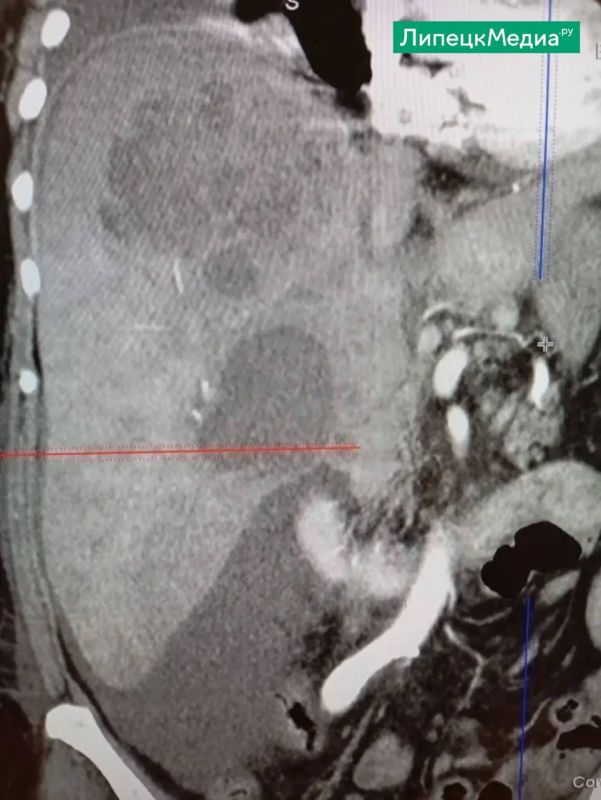

Она длительное время температурила и проходила сложные обследования, но все было безрезультатно.Диагноз был поставлен позже и звучал угрожающе – киста печени, осложненная нагноением.На этой неделе врачи городской больницы «Липецк –...